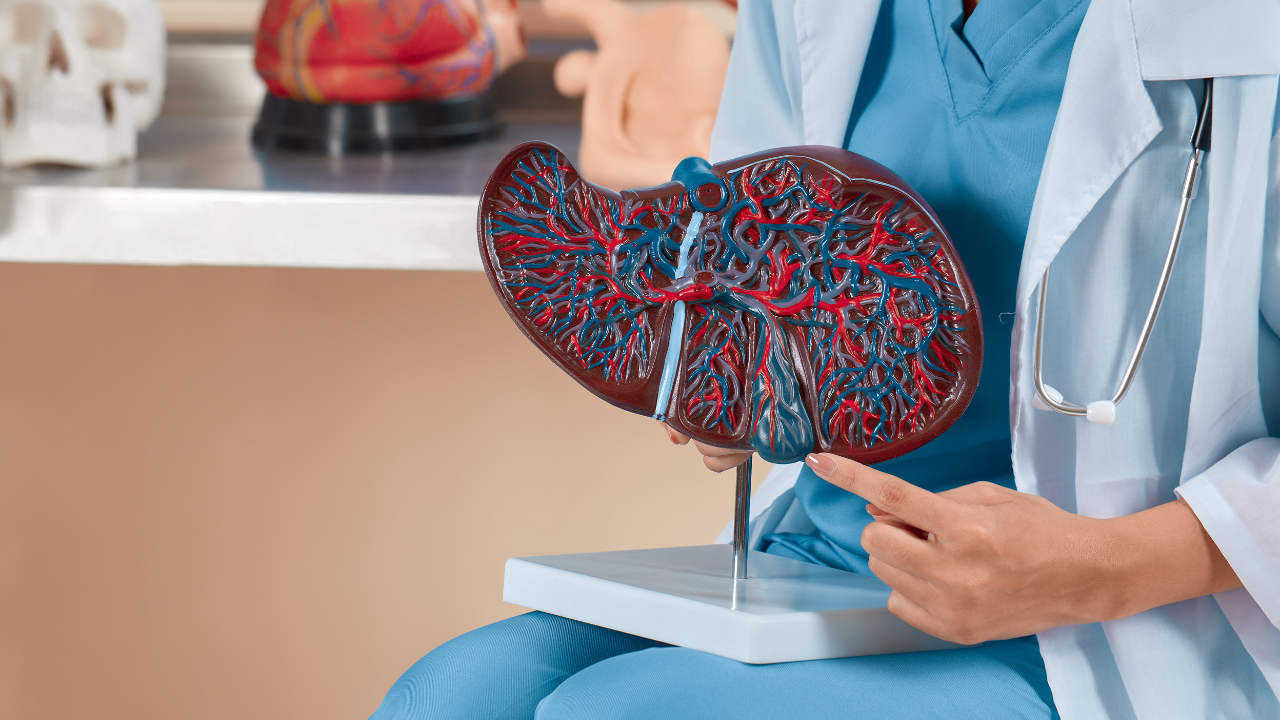

Dave Asprey points out that taking activated charcoal before drinking can reduce not just the hangover the next day but also gas, bloating, and toxic load on the liver. This isn’t magic, it works mechanically. Charcoal sticks to substances like congeners (toxic by-products found in alcohol) and helps move them out of the system more efficiently.